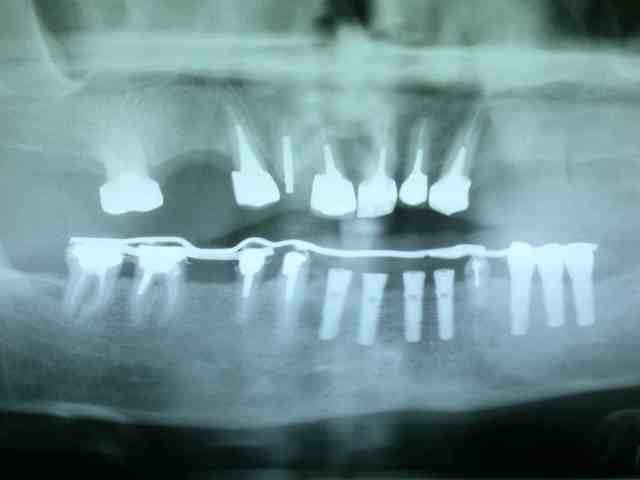

pose de trois implants en 24 25 26 attente de l'ostéointégration au maxllaire et je poursuis sur la prothèse mandibulaire

avulsion de la 34 (vous me suivez toujours) mise en fonction des 4 de devant

bridge transvissé sur 37 36 35 scellé sur fm implantaire sur 32 31 .

couronnes unitaires sur 42 41 (41 mal située position un peu trop lingual : la vue linguale de la photo montre notre solution prothétique pour l'axe)

bridge dentoporté sur 47 46 44 43

pano et photos a suivre les photos sont pas tops car vieil apparei et je vous le rappelle (reflex nauseeux,faut pas aller chercher trop loin quand même , mais vous verrez à la fin on met des écarteurs photos si si...)